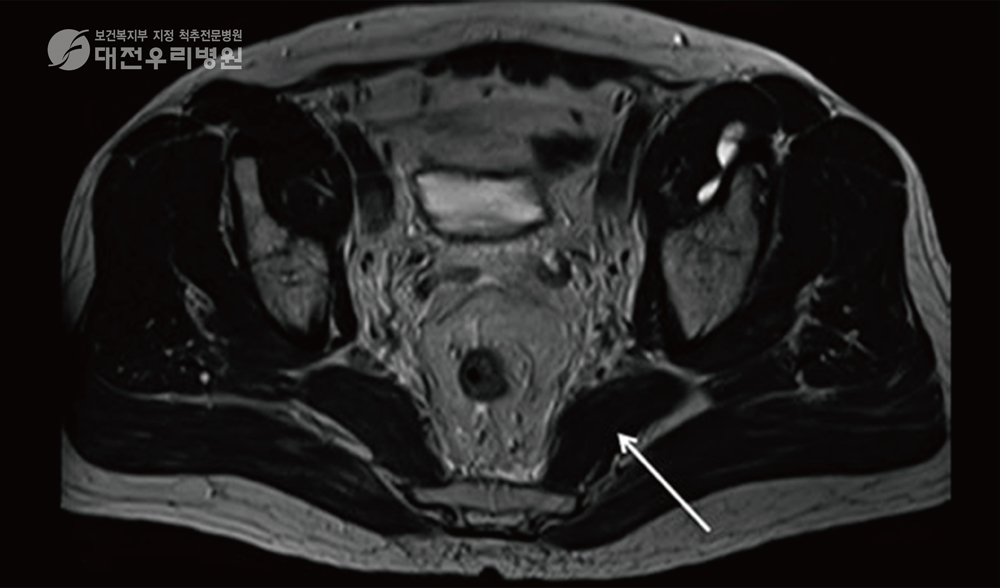

ÃÖ±Ù¿¡´Â ÀÌ»ó±Ù ÁõÈıºÀÌ ÀǽɵǸé Áø´Ü°ú Ä¡·á¸¦ µ¿½Ã¿¡ ÇÒ ¼ö ÀÖ´Â ±ÙÀ° ½Å°æ ÀڱؼúÀ» ½ÃÇàÇÕ´Ï´Ù. ±ÙÀ° ½Å°æ ÀڱؼúÀ̶õ ÅëÁõÀÇ ¿øÀÎÀÌ µÇ´Â ±ÙÀ°, ½Å°æ, °üÀý ºÎÀ§¸¦ IMS ¿ë ¹Ù´Ã·Î ÀÚ±ØÇÏ¿© Ä¡·áÇÏ´Â ÅëÁõ ½Ã¼ú·Î ¹¶Ä£ ÀÌ»ó±Ù ±ÙÀ°À» ¹Ù´Ã·Î Ç®¾îÁÖ´Â Ä¡·áÀÔ´Ï´Ù. ƯÈ÷ ÀÌ Ä¡·á´Â ¾à¹°ÀÌ ¾È µé¾î°¡±â¿¡ ºÎÀÛ¿ëÀÌ ¾ø´Â °ÍÀÌ ÃÖ´ë ÀåÁ¡ÀÔ´Ï´Ù. ±×¸®°í È¿°ú ¸é¿¡¼ ¾àÀ̳ª µµ¼ö Ä¡·á, ¹°¸®Ä¡·áº¸´Ù ÈξÀ ´õ Ź¿ùÇÕ´Ï´Ù. ƯÈ÷ ȯÀÚ¸¦ Ä¡·áÇÒ ¶§ ¾Æ·¡ ±×¸²¿¡¼ º¸µíÀÌ ÃÊÀ½ÆÄ À¯µµÇÏ¿¡ Ä¡·á¸¦ ¸¹ÀÌ Çϰí ÀÖ½À´Ï´Ù. ±×·¯¸é ÀÌ»ó±Ù Á¤È®ÇÑ ºÎÀ§¿¡ Ç÷°ü ½Å°æÀ» ÇÇÇÏ¿© ¿ÀÂ÷ ¾øÀÌ ¾ÈÀüÇÏ°Ô ½Ã¼úÇÒ ¼ö ÀÖ½À´Ï´Ù.